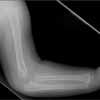

The skull, the long bones of the extremities, and the clavicle are most susceptible to injury following a seemingly insignificant accidental fall.5,6 However, these are the same bones, along with the ribs, that are fractured when a child is intentionally injured. Although serious sequelae, such as depressed skull fractures, can result from a low fall, the vast majority of children do not sustain major injury.5-8

As with skull fractures, rib fractures are of extreme concern. The distal or mid clavicle can be easily injured in an accidental fall, but a fracture of the most medial aspect of the clavicle is particularly worrisome.22 The long bones are commonly injured in an accident, but in a child older than 1 year, the long bones (femur, humerus, tibia, and forearm bones) are also the most common location of non-accidental injury.22

Imaging studies are often necessary in the assessment of an infant or young child with an obvious or suspected injury. The skeletal survey (Table 3) is recommended and is mandatory in all cases of suspected abuse in children younger than 2 years.24 However, it has little value in children older than 5 years.25 Patients between ages 2 and 5 years are assessed on an individual basis.

If clinical findings point to a specific injury site, that anatomic region should be evaluated with a radiograph--regardless of the child's age.25 An experienced radiologist should be present while imaging is performed to ensure that high-resolution images of good quality are obtained. If the initial skeletal survey is unremarkable but abuse is still strongly suspected, a repeated skeletal survey in 2 weeks may offer greater yield in discovering occult fractures.26 A bone scan is another option for searching for occult fractures: the need for this modality is determined on a case-by-case basis.